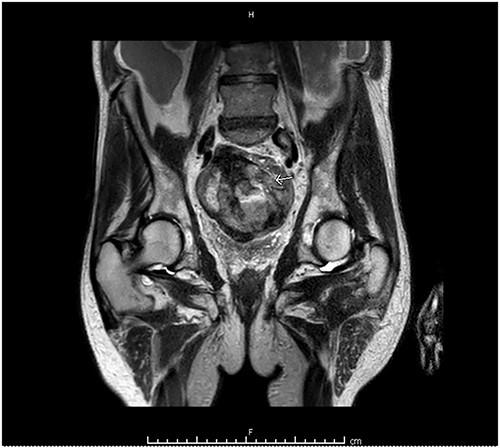

Computed tomography (CT) of the abdomen and pelvis showed moderate-to-large volume hemoperitoneum. The epicenter of the hemorrhage appeared to be in the pelvis where a rectovesical hematoma mass measured 8.2 × 7.0 cm (Fig. 1). The center of the hematoma raised suspicion for active hemorrhage consistent with contrast blush. No source of bleeding was identified on arteriography. Magnetic resonance imaging (MRI) with contrast ensued and suggested small bowel segment involvement in the lateral side wall of the hematoma within the pelvis (Fig. 2). Considering the patient presentation, imaging, and declining hemoglobin (Hb 8.3 g/dl), the patient was brought to the operating room for an exploratory laparotomy. Old blood was immediately encountered upon entering the abdomen during surgery. An exophytic mass, about 5 cm in diameter located on the antimesenteric border of the mid jejunum, was noted. The mass was actively oozing and was determined to be responsible for the hemoperitoneum. Specimens from the pelvic side wall, small bowel, and the hematoma were collected and sent to pathology. Small bowel resection with anastomosis was performed on the main tumor, though it was thought that residual disease was left. All segment pathology diagnoses showed over 5 cm with 11 mitoses per 5 mm2 GIST with associated blood clot, confirming stage 4 disease.

MRI abdomen and pelvis with contrast identified small bowel involvement in the lateral side wall of the hematoma within the pelvis.